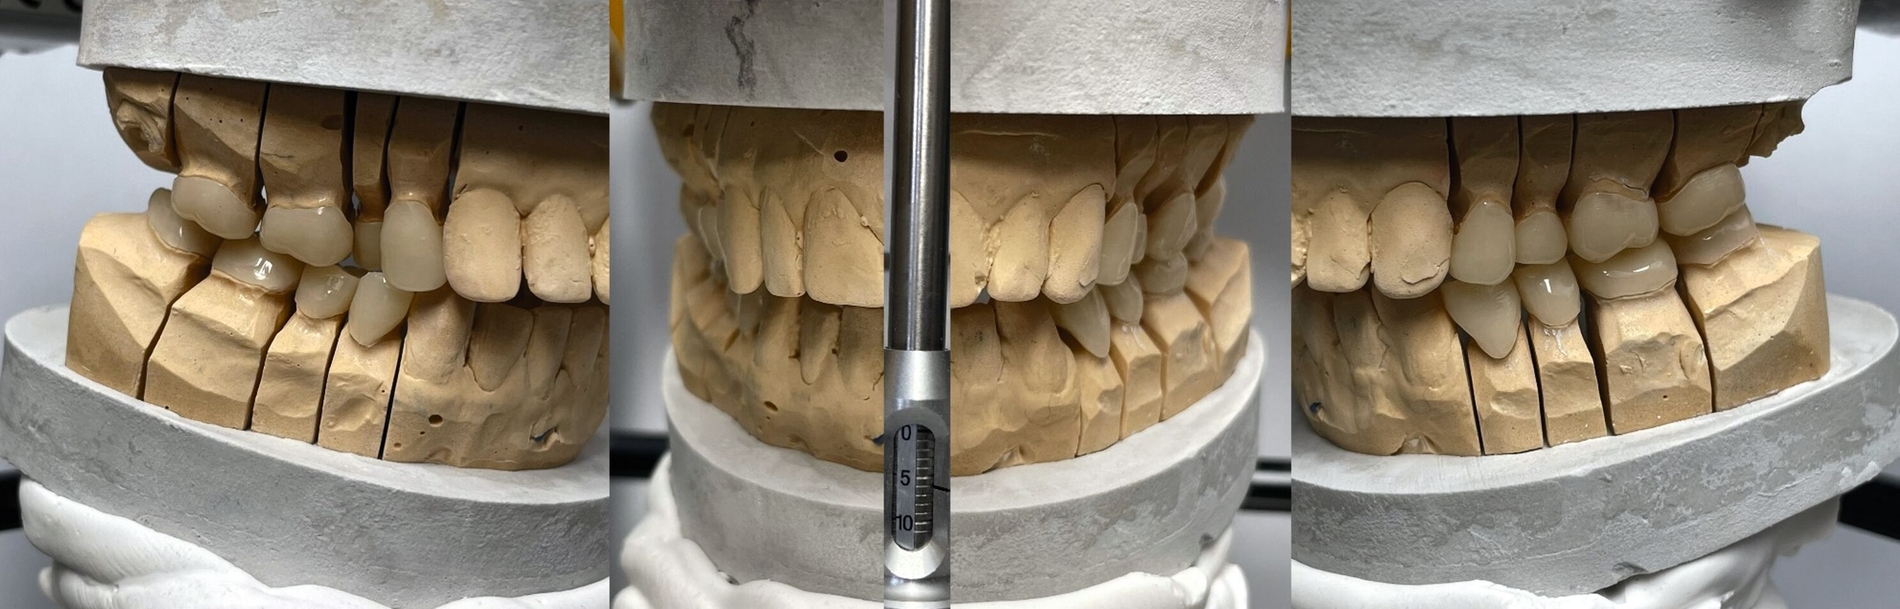

Klinisch zeigte sich ein kariöses Wechselgebiss mit generalisierten Verfärbungen und rauer Schmelzoberfläche. Mehrere Milch- und bleibende Zähne wiesen aktive kariöse Läsionen auf. Zahn 64 war zusätzlich druckdolent und gelockert, mit einer vestibulären Schwellung der Gingiva. Zudem bestanden eine Mittellinienabweichung, ein Overbite von vier Millimetern und ein Overjet von elf Millimetern (Abbildung 1). Extraoral fiel ein fliehendes Kinn mit inkomplettem Lippenschluss und hyperaktivem Musculus mentalis auf. Röntgenologisch waren alle Zähne angelegt, der Zahnschmelz zeigte jedoch eine reduzierte Opazität (Abbildung 2). Eine genetische Abklärung wurde von den Erziehungsberechtigten aus ethischen Gründen abgelehnt.

Nach der Extraktion von Zahn 64 wurden die übrigen kariösen Milchzähne nach Konditionierung (Prime&Bond NT, Dentsply Sirona) mit Kompomer (Dyract extra, Dentsply Sirona) versorgt. Für die Frontzahnbehandlung wurde zunächst ein Wax-up auf Situationsmodellen erstellt (Abbildung 3), anschließend eine Silikonformhilfe angefertigt. Nach Reinigung und 3-Schritt-Etch-and-Rinse-Konditionierung (OptiBond FL, Kerr) unter relativer Trockenlegung wurden die Zähne in Mehrschichttechnik mit einem Mikrohybrid-Komposit (Herculite XRV, Kerr) versorgt. Die Seitenzähne wurden wegen des ausgeprägten Würgereizes unter absoluter Trockenlegung mit fließfähigem Komposit (Tetric flow, Ivoclar Vivadent) temporär rekonstruiert (Abbildung 4).